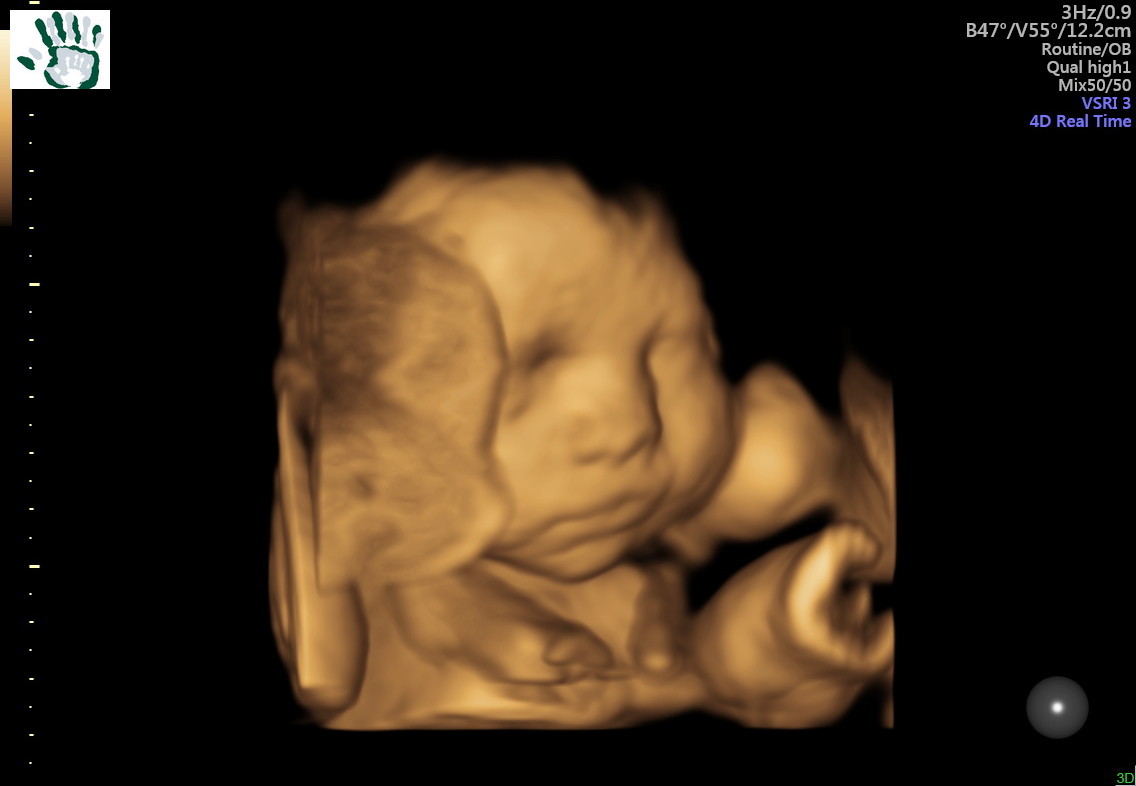

• We got a better 3D picture of her face. Such a precious little face. If you can't tell, I'm falling more and more in love!

Doesn't it just hit you to your core when you see their faces in 3-D? I haven't seen mine yet and I'm hoping they will do it for me just once. Maybe if I beg.